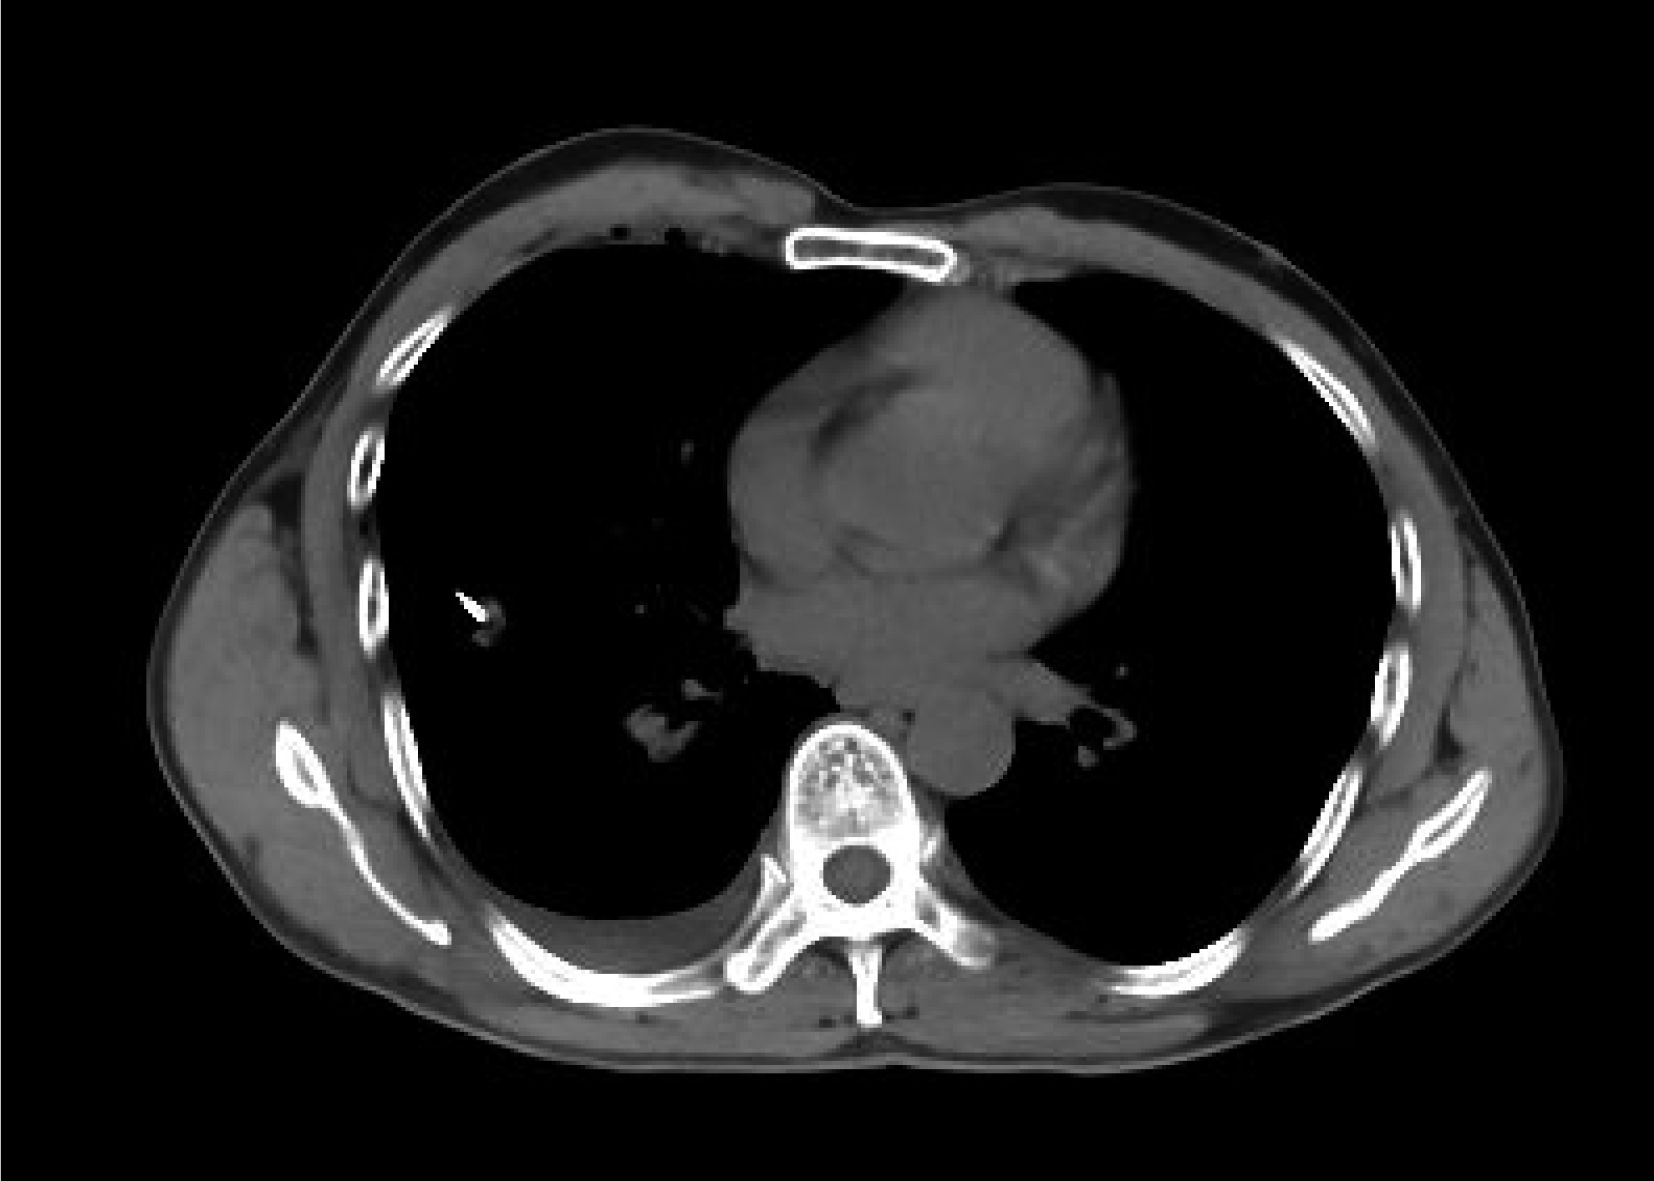

1.2.2 擺位 根據 CT 提示腫塊具體解剖位置,當病灶不清或者胸腔積液掩蓋含有不張的肺組織時應該 CT 增強顯影。當病灶距離前胸壁近時選擇仰臥位(圖 1 和圖 2),相反則選擇俯臥位(圖 3~6);如果病灶靠近側胸壁選擇側臥位;有時肩胛骨遮擋時選擇雙上肢放置于身體兩側或者雙手抱頭。將金屬絲放置于病灶周圍區域,長軸與身體長軸平行,與皮膚緊貼,膠布固定,囑患者平靜吸氣末閉氣,行 CT 掃描定位,對于小病灶應選擇更多影像圖片為宜。

1.2.3 穿刺 采用美國 COOK 公司生產的 18G 彈簧式活檢槍進行穿刺。仔細分析影像圖、選取進針路徑、穿刺角度、測量、調整進針深度(圖 7和圖 8);選擇最佳層面,避開危險血管、肺大皰、骨頭及其他重要臟器,標記穿刺點;戴無菌手套,消毒并鋪洞巾,2% 利多卡因逐層麻醉,按預定進針角度、路徑迅速進針;穿刺預定深度后 CT 掃描,確認針尖是否到達病灶,如果能穿刺病灶邊緣則最好(圖 7和圖 8);囑患者平靜吸氣末閉氣,拔出針芯,按下活檢槍,切割組織,再次套回針芯,組織放入 10% 福爾馬林液固定;重復多次不同方向部位取材,盡量采集有效標本;給予凝血酶止血,最后拔出套管及針芯,消毒穿刺點,敷料加壓覆蓋穿刺點;再一次 CT 掃描查看是否有氣胸、出血等并發癥,確認無嚴重并發癥后返回病房,組織送檢。